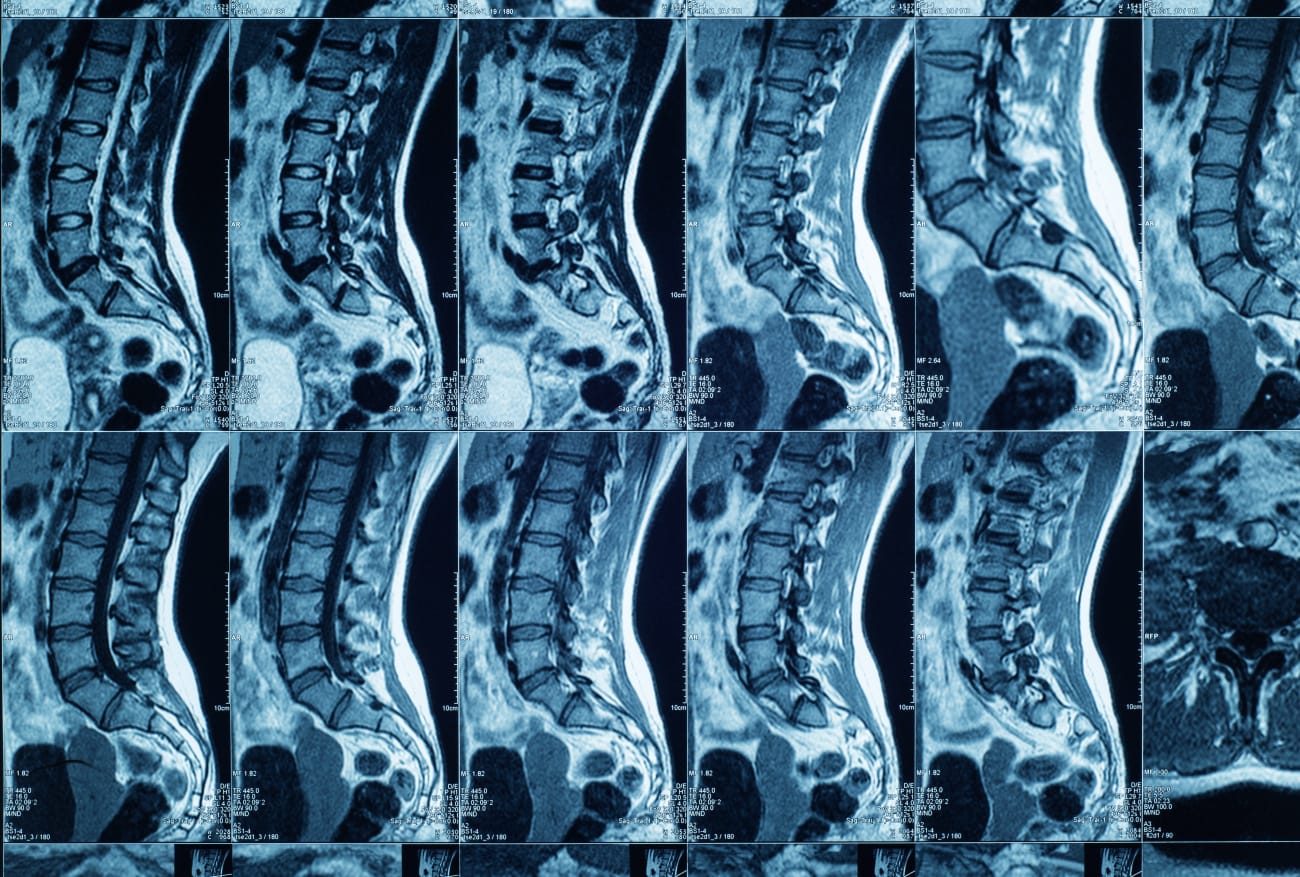

An electromyogram performed by neurologist Omid Motabar showed cervical radiculopathy from the disk herniation, and an MRI showed problems in several spots along the cervical spine. Some of those issues were due to the patient playing sports his entire life, including many years of boxing, which had led to shoulder dislocations and rotator cuff surgery. Without surgery, the patient risked permanent pain, weakness and numbness in his left arm.

Lin and his neurosurgery colleagues also perform minimally invasive microdiskectomies for patients with herniated disks in the lumbar spine. Like artificial cervical disk replacement, this outpatient procedure also involves making a smaller incision for surgery, which promotes faster healing and reduces postoperative pain.

While many patients with bulging disks can heal with nonsurgical interventions, those who have neurologic deficits such as muscle weakness or numbness that can be confirmed via MRI are good candidates for microdiskectomy.